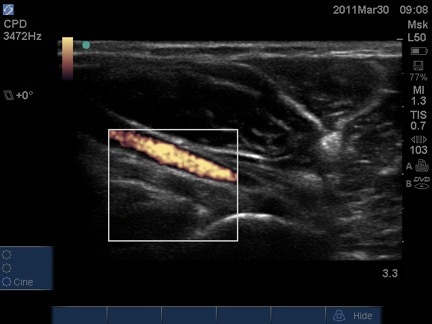

Elbow Distal Biceps Tendon Long Axis Image